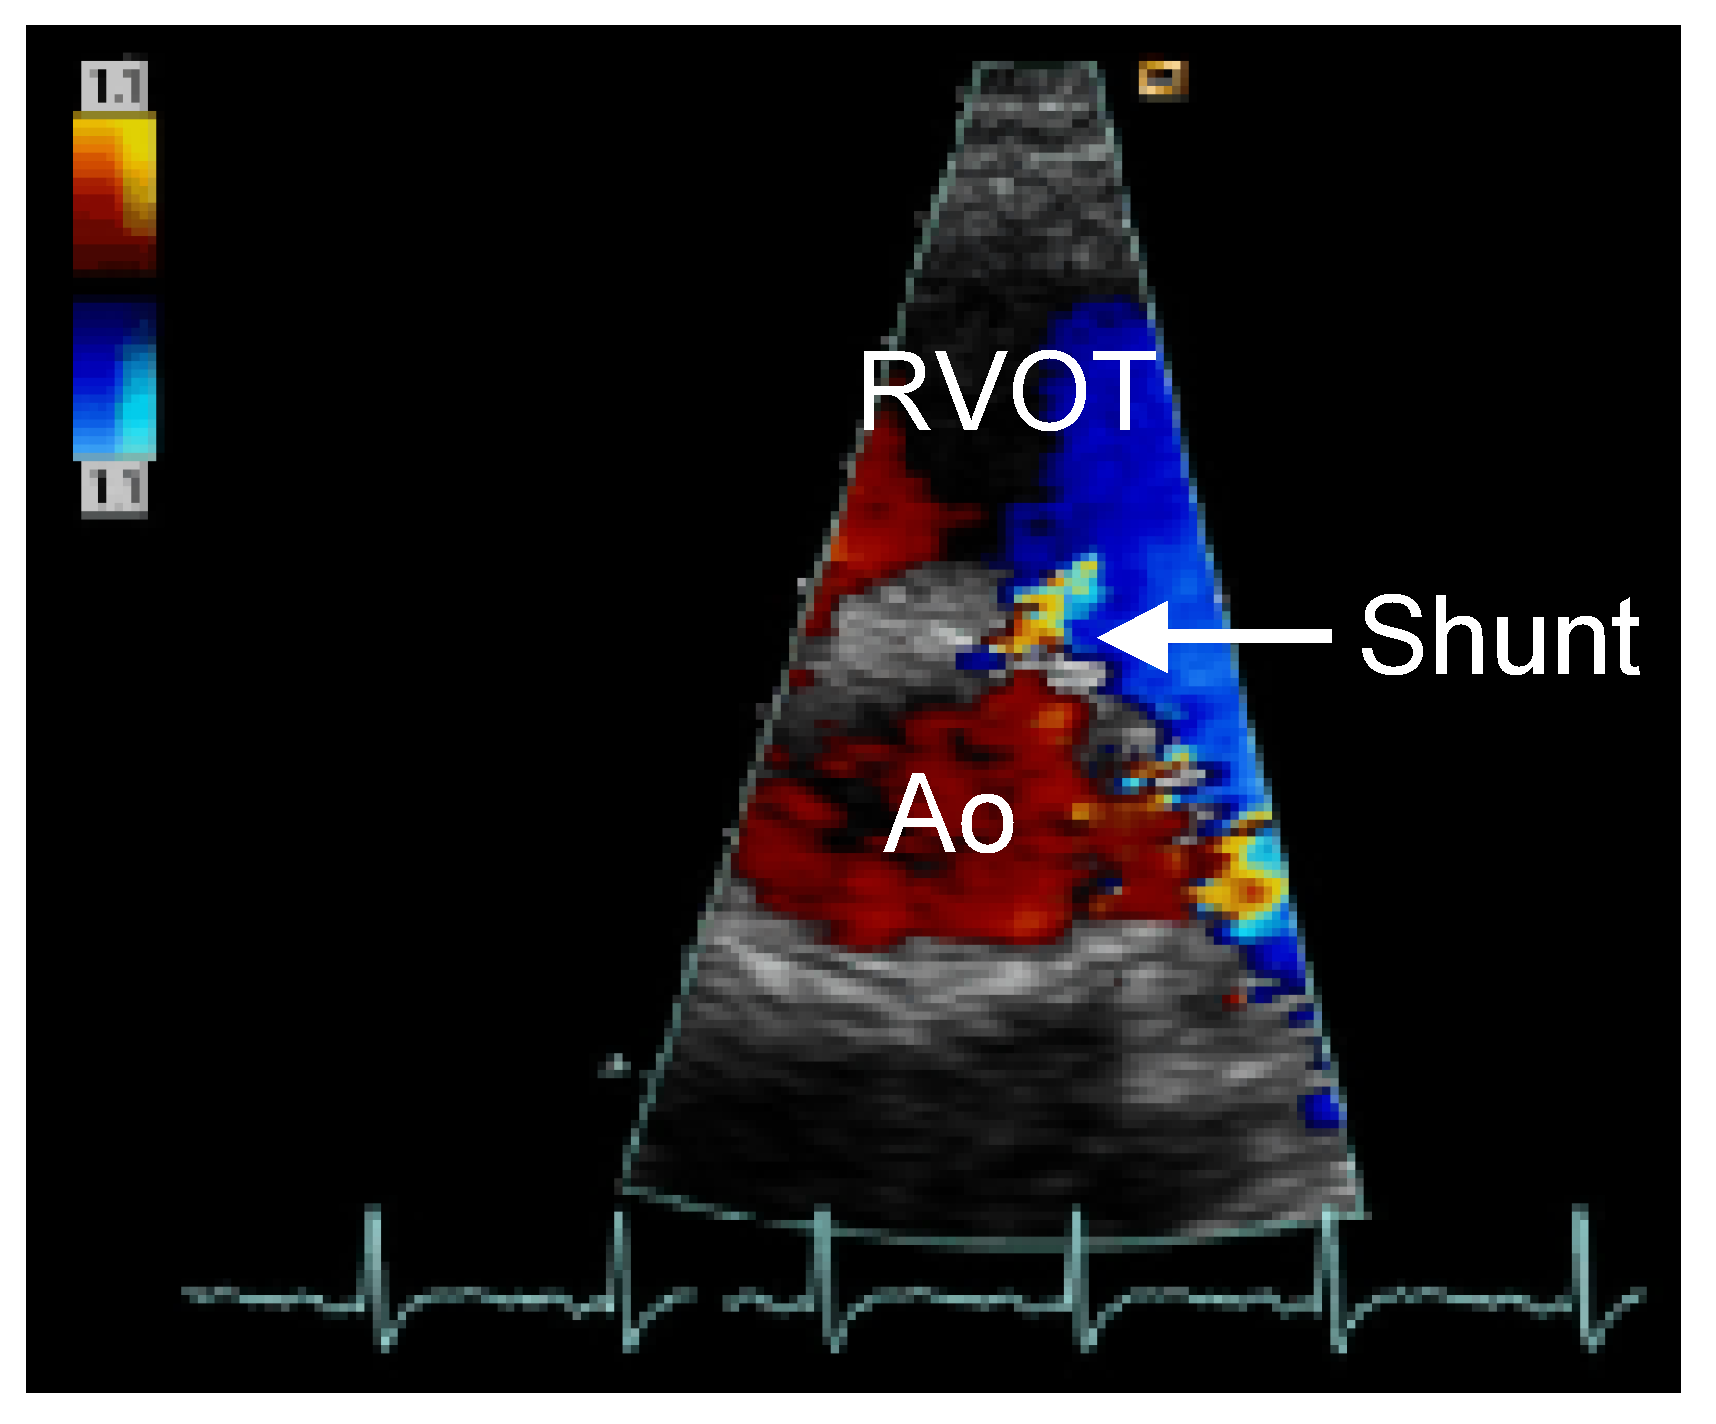

Straight into the Heart: Sinus of Valsalva Injury

Case description